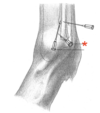

Describe the needle access of the fetlock joint (distal palmar/plantar approach)

- Between:

- Lateral proximal sesamoid bone

- Base of Ph-I

- Dorsoproximal needle direction

Dorsal from the lateral digital artery

The limb should be weight-bearing